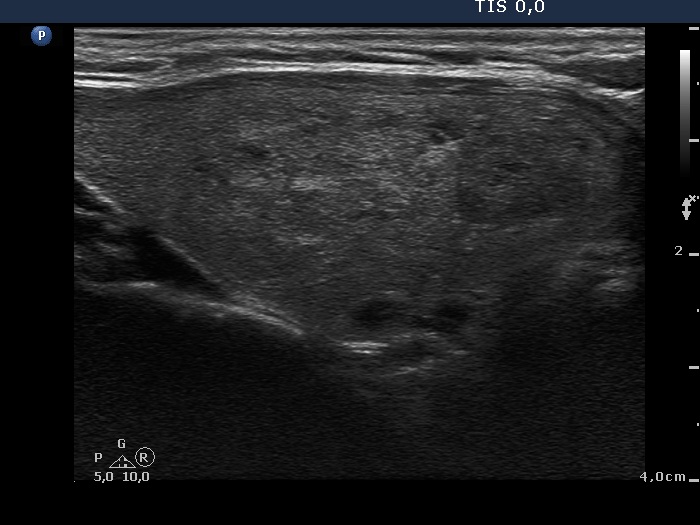

First examination (first row of images):

Clinical presentation: A 57-year-old woman was referred for aspiration cytology of a multinodular goiter has been known for more than two decades. The patient had no complaints.

Palpation: a multinodular goiter without any nodule suspicious on palpation.

Functional state: euthyroidism with TSH 0.96 mIU/L.

Ultrasonography. The thyroid was echonormal and was composed of multiple nodules. Most of them were hyperechogenic or minimally hypoechogenic. There was a hypoechogenic nodule presenting bright hyperechogenic granules in the upper part of the left lobe.

Cytology resulted in benign colloid goiter.